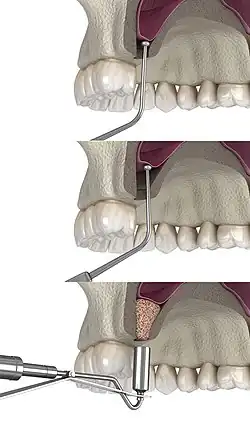

The procedure is performed intraorally, where the surgeon makes an incision into the gum. Once the incision is made, the surgeon then pulls back the gum tissue, exposing the lateral bony wall of the sinus. The surgeon then creates a "window" into the sinus, exposing the Schneiderian membrane. The membrane is separated from the bone, and bone graft material is placed into the newly created space. The gums are then sutured closed, and the graft is left to heal for 4 to 12 months.[8]

The graft material can be either an autograft, allograft, xenograft, alloplast, a synthetic variant, or a combination of both.[9] Studies indicate that the lifting of the sinus membrane might result in new bone formation due to the principles of guided bone regeneration.[10] The long-term prognosis for the technique is estimated at 94%.[11]